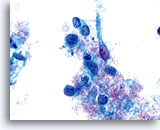

Carcinosarcome

Présence d’éléments glandulaires néoplasiques et de débris nécrotiques permettant d’établir un diagnostic de carcinosarcome.

60X